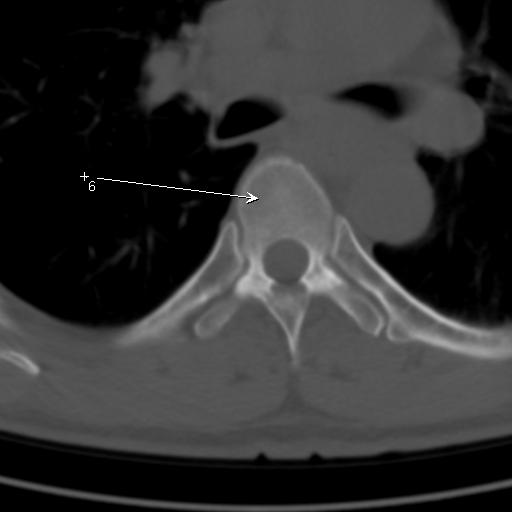

标题: CT25189:胸椎ct,请会诊!

既往食管癌,现行ct检查!

仅见椎体退行性改变

中上段食道癌,椎体轻度退变。

椎体退行性改变,食管癌。

支持中上段食道癌,椎体轻度退变,必要时做ect。

支持中上段食道癌,椎体轻度退变。